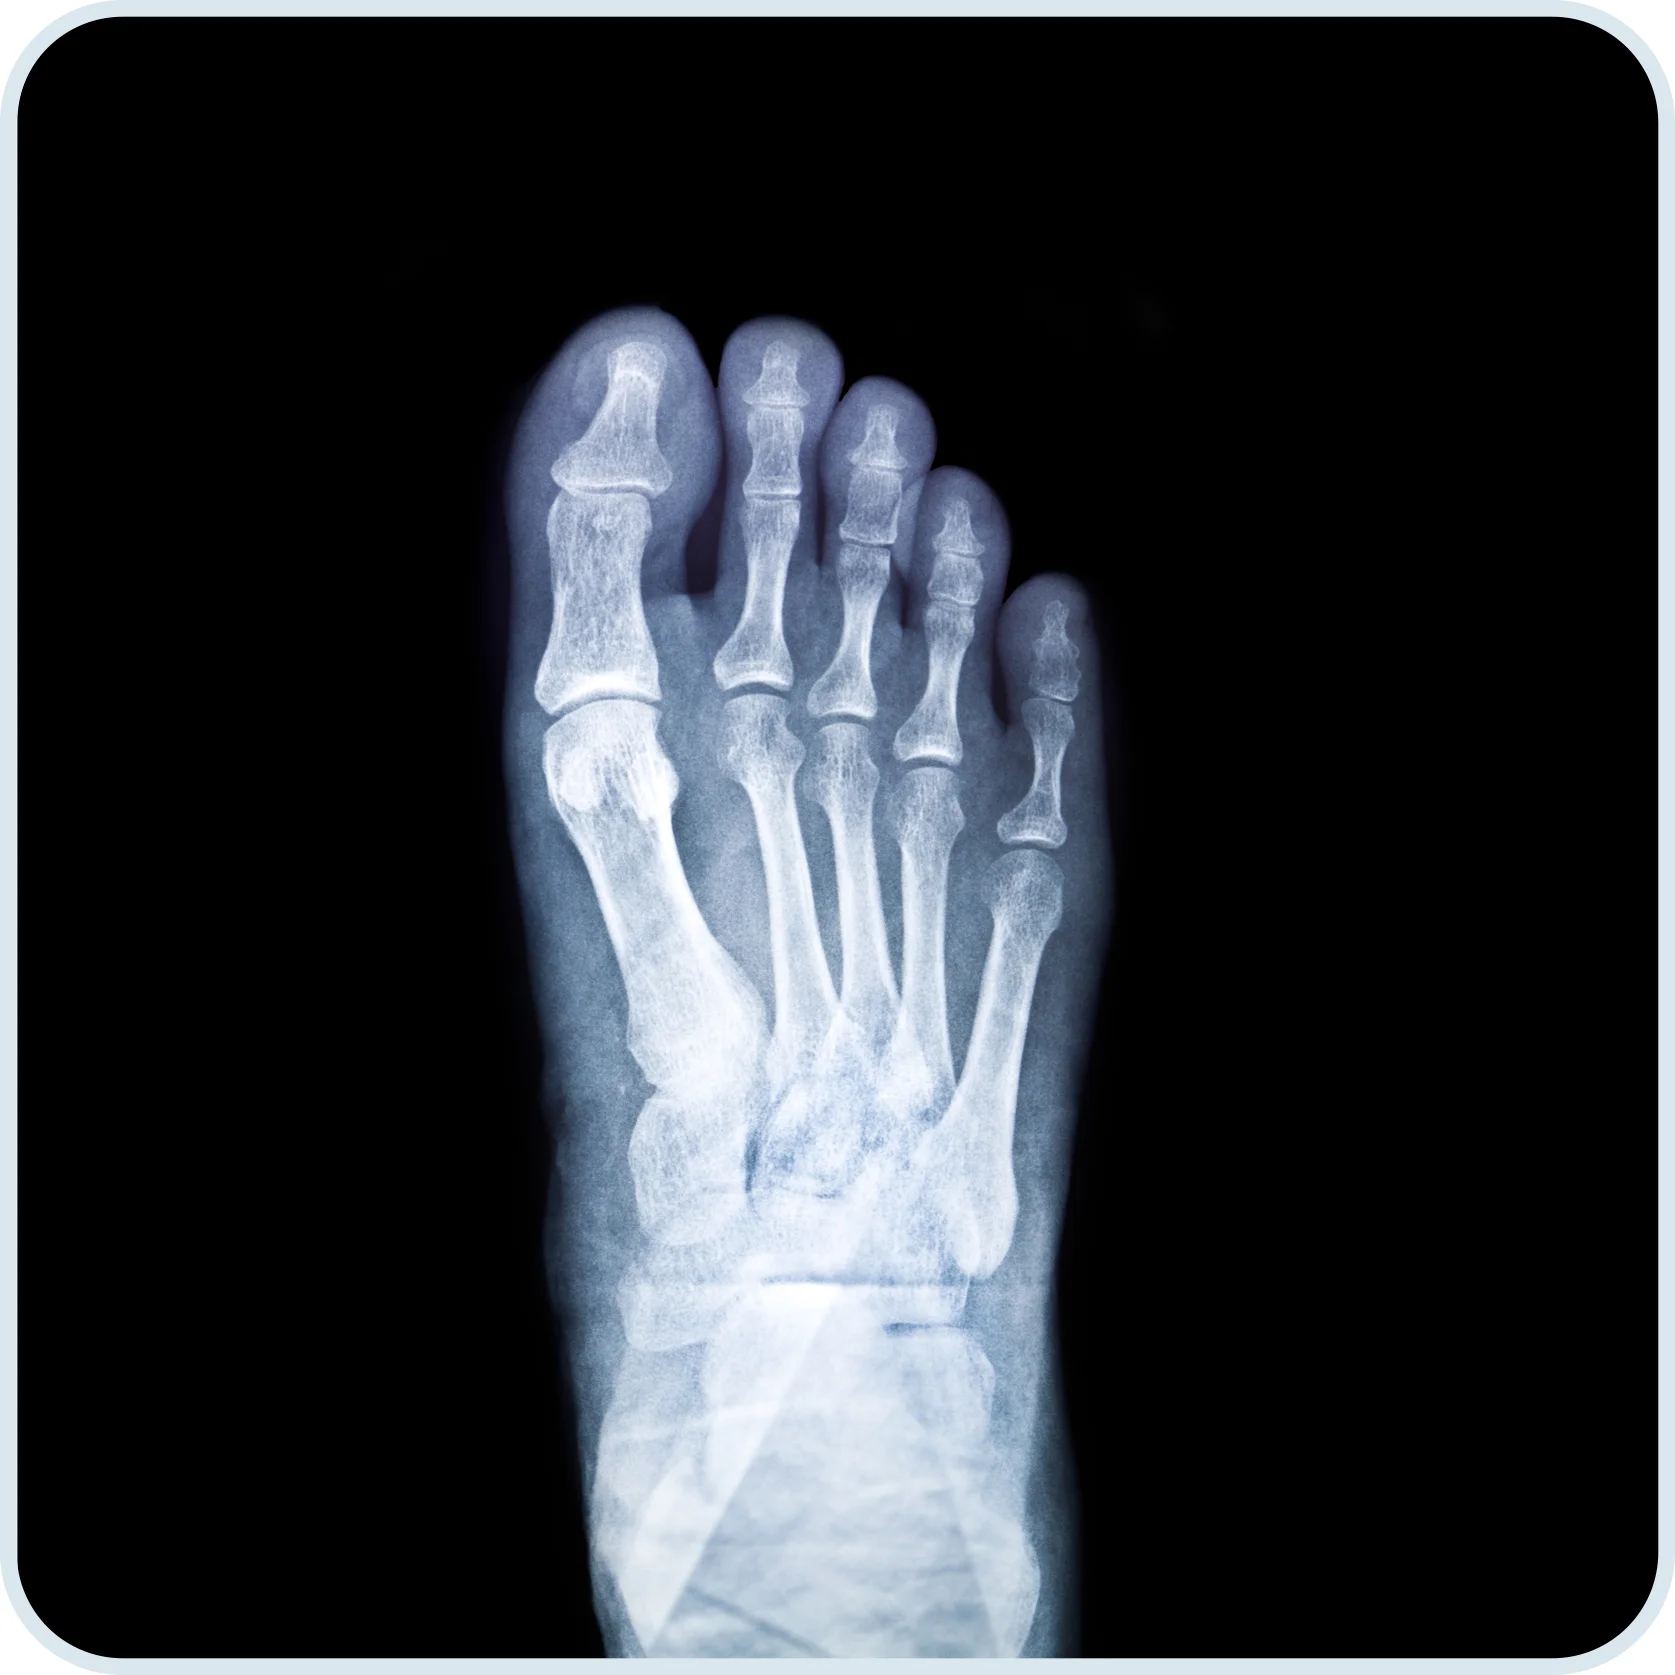

A:已侵蝕及變形的關節和軟骨不能再復原,故此及早檢測和治療類風濕關節炎十分重要。